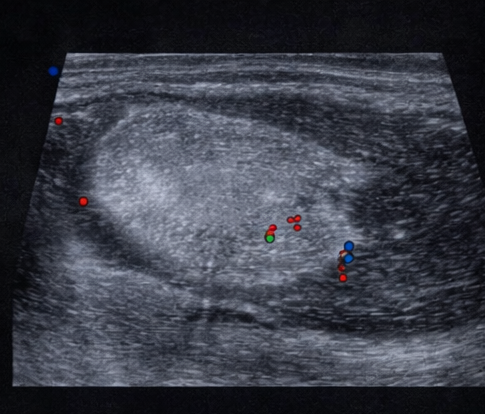

Ultrasound examination of the swelling revealed a well-circumscribed, homogenous, hyperechoic lesion located in the subcutaneous tissue. The lesion showed no internal calcification or cystic components and minimal internal vascularity on Doppler evaluation, favoring a benign fatty lesion.